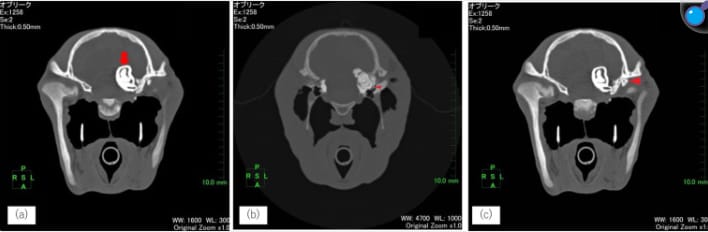

Cranial computed tomography (transverse plane) in case 1.

a: Ectopic tooth located within the skull (red arrow). b: Ectopic tooth root located near the inner ear (arrowhead). c: A free, bone-like structure (arrowhead) was observed on the ventral side of the temporal bone.